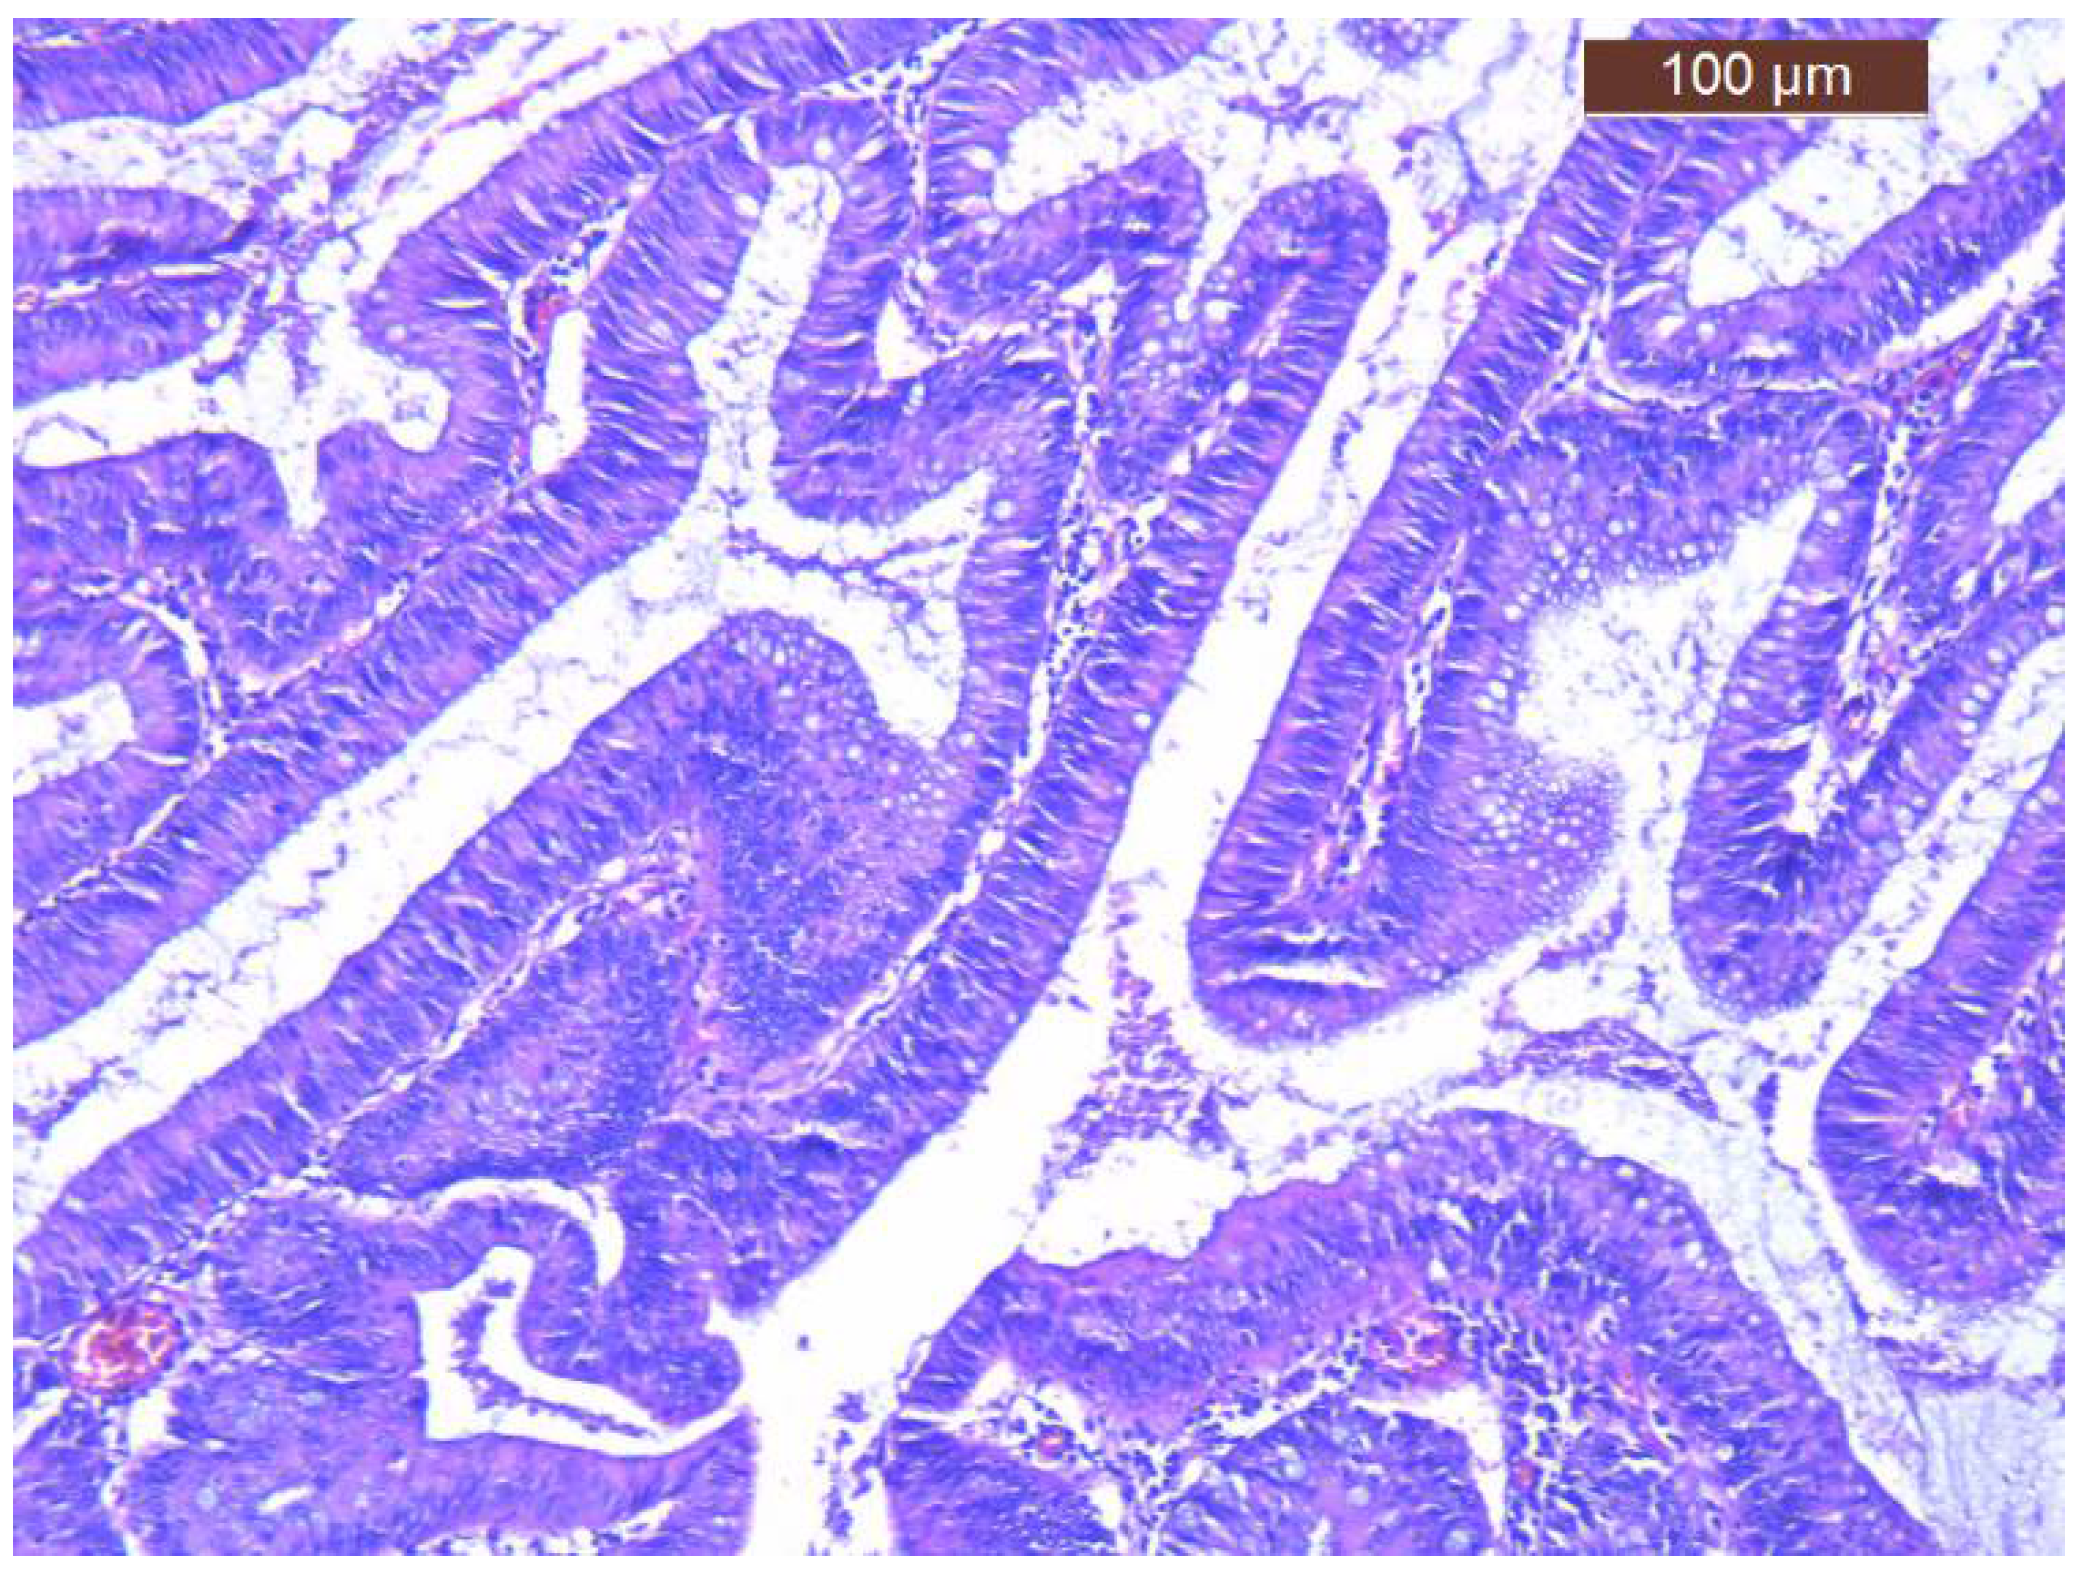

Regarding treatment, volume and electrolyte replacement was maintained, with gradual correction of hyponatremia, hypokalemia and azotemia. For the definitive treatment the patient was transferred to the Surgical Department and successfully underwent left hemicolectomy (Hartmann procedure) (Figure 4). The histology of postoperative specimen reported tubulo-villous adenoma with low-grade dysplasia and several foci of high-grade dysplasia, without any signs of infiltration in muscularis mucosae and beyond it (Figure 5). There were also examined 12 lymph nodes, with non-specific reactive inflammatory changes. Corroborating histopathological aspects with clinical and biochemical features, the diagnosis of McKittrick-Wheelock syndrome was considered.

Figure 5.

Histology of resected specimen (tubulo-villous adenoma with low-grade dysplasia and several foci of high-grade dysplasia).